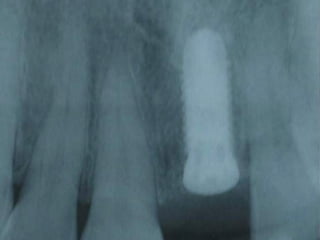

This document discusses several dental implant cases where porcelain crowns were used to restore teeth. It describes the process for each case, including placing implants, attaching provisional crowns, modifying the crowns, adding porcelain, and delivering the final restoration. Photos show before and after images for each case, which include replacing premolar teeth, bridges, and full upper dental arches.